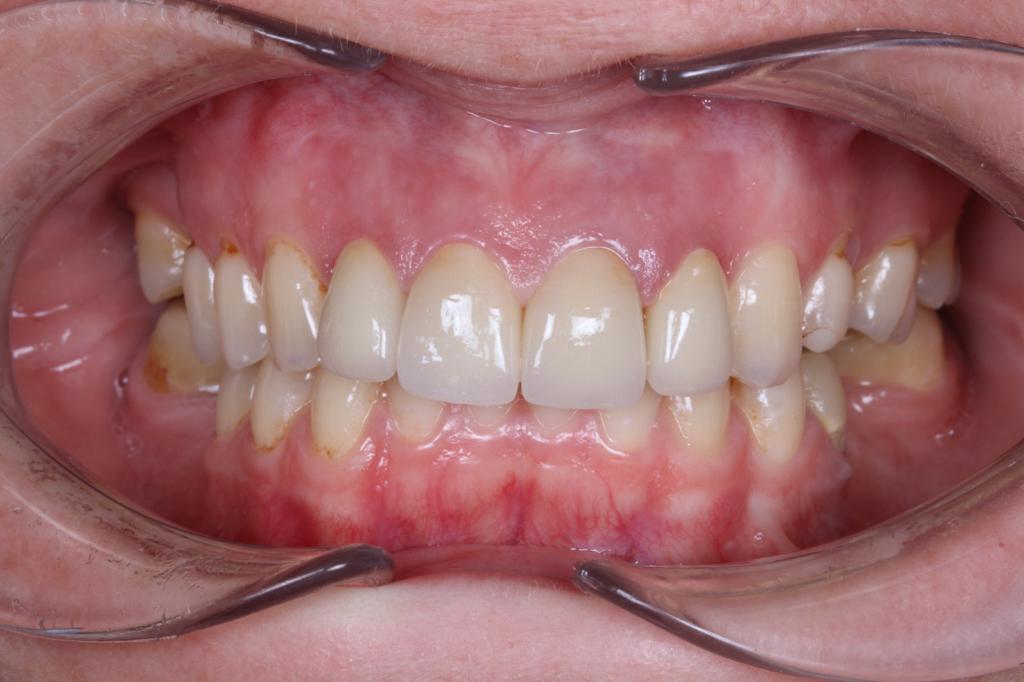

Виниры полевошпат

Пациентка обратилась в клинику на профилактический осмотр , было выявлено, что под ранее установленными винирами есть кариозные поражения. Наш доктор Кациев М.М. принял решение заменить виниры с 13 по 23 зубы.

Предварительно, перед установкой новых виниров , было проведено лечение по кариесу. Пациентка осталась довольна.